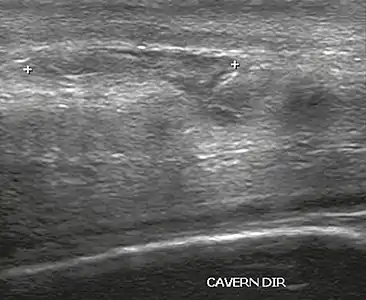

The corpora cavernosa are homogeneous and relatively hypoechoic cylindrical structures lined with tunica albuginea, a thin membrane that has a thickness of approximately 2 mm when the penis is flaccid and 0.25 mm when it is erect. The corpus spongiosum, a ventral, medial body that is more echoic than the corpora cavernosa, is also covered by the tunica albuginea and contains the urethra. As can be seen in Figures 1 and 2, it is more dilated and prominent in its proximal segment, known as the bulb, and in its distal segment, constituting the glans. Buck's fascia is superficial to the tunica albuginea and covers all of the structures described.[1]

Venous drainage is performed by the deep and superficial dorsal veins of the penis. The dorsal arteries of the penis are located adjacent to the deep dorsal vein and a cavernous artery is located in the center of each corpus cavernosum. On color Doppler, the cavernous arteries present single phase flow. In the flaccid penis (Figure 3), the normal cavernous arteries show a systolic peak between 11 and 20 cm/s. At the beginning of erection, the systolic and diastolic flows undergo progressive increases. When vein occlusion begins, the diastolic flow decreases progressively, and once stiffness is established, it becomes negative.[1]